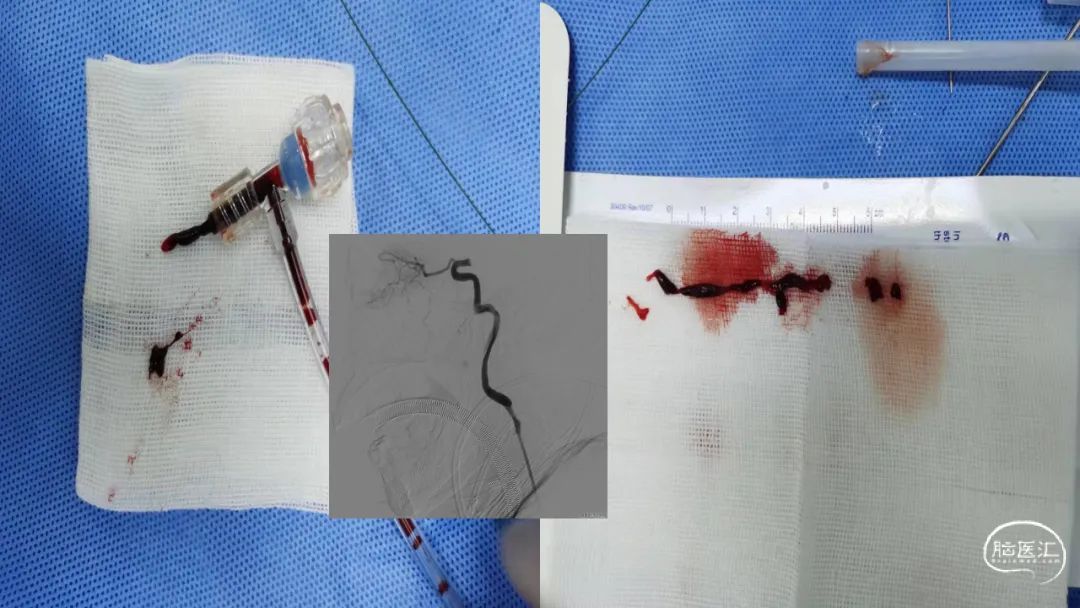

本期主讲┃魏铭

天津市环湖医院主任医师

美国芝加哥拉什医学中心(Rush University Medical Center)神经外科脑血管病中心访问学者。专业方向为脑血管病的介入治疗,如急性脑梗的动脉取栓;颅内动脉瘤和脑血管畸形的介入治疗;缺血性脑血管病颈动脉、椎动脉等颅内外支架植入等。致力于神经介入技术和材料的创新性研究,参加多项国家级及省部级科研项目、承担天津市科技支撑重点项目一项,天津市卫计委科技攻关项目一项,发表SCI论文10余篇,获天津市科技成果一项,天津市科技进步奖一项,获得发明专利一项。现任中国卒中学会神经介入分会青年委员,中国卒中学会脑静脉病变分会委员,北京市神经内科学会青委会常委,天津市医疗健康学会脑病专业委员会副主任委员,中国中医药信息学会中西医结合介入分会理事。